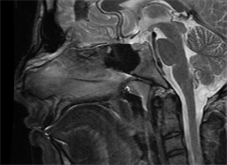

Under general anesthesia, infiltration of the dorsum of the nose was done with 1 in 100,000 lignocaine solution. Navigation protocol [Figure 3] is used because we were operating in critical area like skull base & Dura.

Figure 3. Navigation protocol.